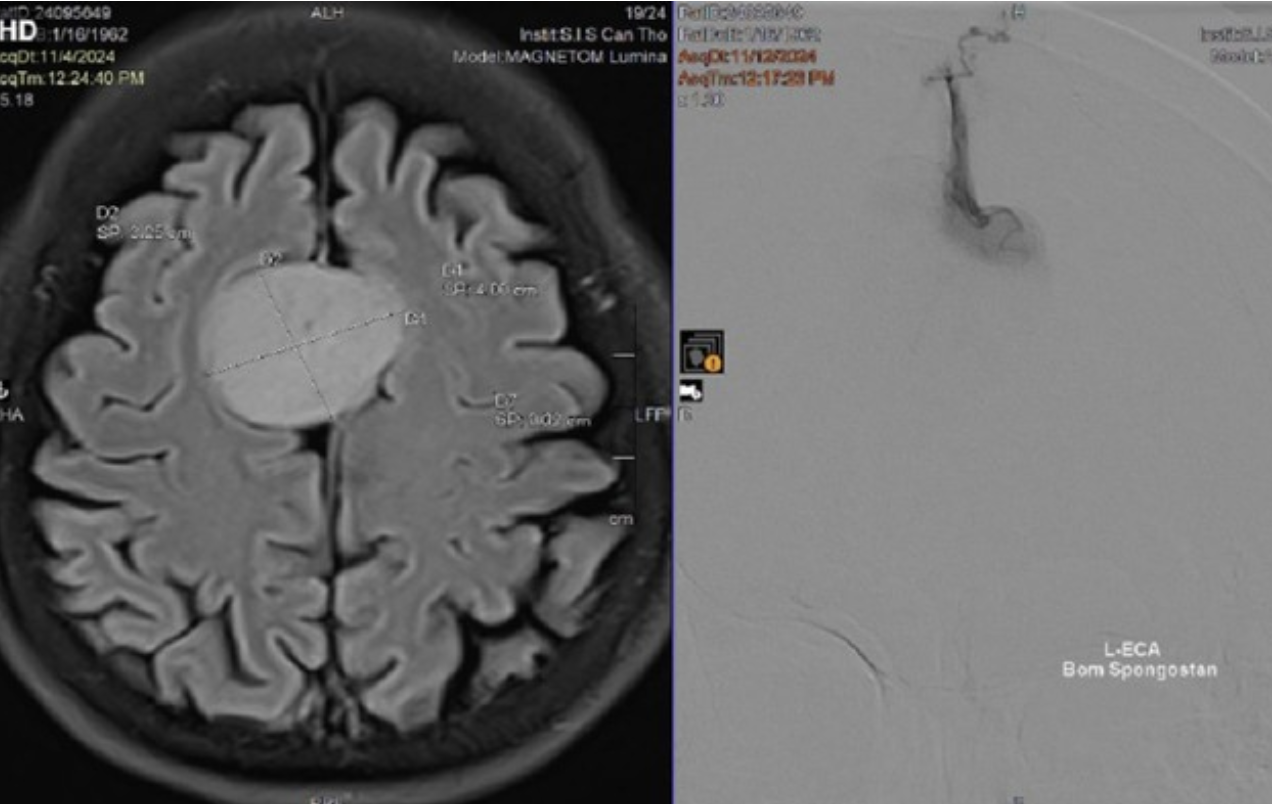

Khối u não có kích thước lớn nằm giữa đỉnh đầu của người bệnh

Tuy nhiên, trên hình ảnh kiểm tra ghi nhận, bệnh nhân có khối u não kích thước lớn (35 x 40mm) nằm giữa đỉnh đầu, chấn thương do tai nạn không liên quan đến khối u này. Tai nạn giao thông trở thành tình huống may mắn giúp bệnh nhân được chẩn đoán, điều trị khối u não. Để tránh biến chứng nguy hiểm đến tính mạng của người bệnh, các bác sĩ đã thực hiện tắc mạch, phẫu thuật loại bỏ khối u.

Sau gần 4 giờ, các bác sĩ đã bóc tách thành công toàn bộ khối u khỏi mô lành. Sau mổ, sức khỏe bà T. đã bình phục tốt.